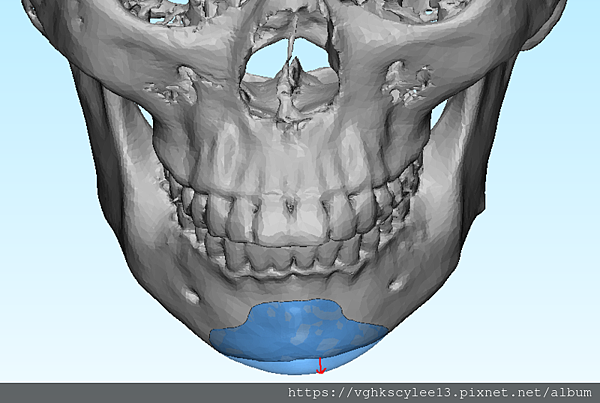

下圖:不對稱下巴骨架,透過列印技術可以做出調整下巴歪斜的假體組合。

歪斜下巴調整性假體設計

下圖範例:歪斜不對稱下巴經3D導航客製化導航矯正性假體

(下圖)3D模擬後工程師版的設計下巴假體的外型。

經過李醫師醫師對客戶外型的判斷,修改工程師的設計,建議更改後的假體模型(下圖)

(上圖)經過李醫師醫師對客戶外型的判斷,修改工程師的設計,建議更改後的假體模型。所以嘍,醫師的美感與專業度必須要做判斷,3D列印只是精準工具但是必須有專業醫師的判斷才可以完美!

下圖: 在李醫師確認後完美精準例印

窄小後縮的下巴,以精準3D列印技術來客製化醫師判斷後的外型下巴假體,一起改善嘴形相對的狀態。

窄小後縮的下巴,以精準3D列印技術來客製化醫師判斷後的外型下巴假體,一起改善嘴形相對的狀態。

3D模擬後 列印出吻合的設計下巴假體